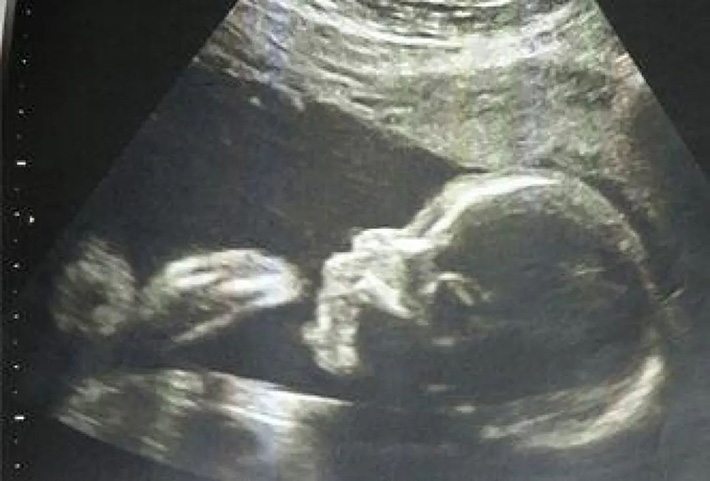

El llamado ultrasonido B es una tecnología que utiliza el ultrasonido como medio para diagnosticar enfermedades a través de la ecografía del ultrasonido que atraviesa el cuerpo humano.

Debido a la buena penetrabilidad y anisotropía de las ondas ultrasónicas, es posible obtener imágenes del interior de los objetos mediante absorción, reflexión, refracción y difracción. En medicina, el principio de funcionamiento de la ultrasonografía es transmitir ondas ultrasónicas al cuerpo humano. Cuando encuentra varias interfaces en el cuerpo, se reflejará y refractará, y se absorberá y atenuará en diferentes grados en diferentes tejidos. Estos procesos se pasan a través de instrumentos. Se reflejarán diferentes formas de onda, curvas e imágenes, y los médicos pueden diagnosticar enfermedades analizando estas imágenes.

Las técnicas de diagnóstico que utilizan ultrasonido se dividen en tipos A, B, C y D. El diagnóstico de enfermedades en forma de amplitud de onda de sonido se denomina "visualización unidimensional", porque la primera letra de la amplitud en inglés Amplitud es "A", también conocida como ultrasonido A; y el diagnóstico de enfermedades en el modo de brillo en escala de grises se denomina "visualización bidimensional". La primera letra de Brightness en inglés es "B", también conocida como B-ultrasonido. Los métodos de diagnóstico tipo M y tipo D se utilizan generalmente para controlar el corazón y el flujo sanguíneo respectivamente, y también se denominan métodos de diagnóstico por ecocardiografía y ecografía Doppler, que no se tratarán aquí.

El equipo de inspección por ultrasonido B se compone principalmente de sonda, host, fuente de alimentación, pantalla, carcasa y periféricos. Entre ellos, la parte de la sonda se compone de un chip, un bloque de absorción de sonido, una capa correspondiente y un bloque de absorción de sonido; el host y la pantalla están compuestos por una computadora y una pantalla que procesan información y se utilizan para recibir la información recopilada por la sonda. A través del cálculo y el procesamiento, varios datos Conviértalos en una imagen, muéstrelos en un monitor o imprímalos; la fuente de alimentación y la carcasa son instalaciones auxiliares que proporcionan energía y protección para el host y la sonda.

La tecnología de diagnóstico de ultrasonido B ahora se usa cada vez más, como el ultrasonido endoscópico, el ultrasonido mejorado con contraste, las imágenes tridimensionales, las imágenes elásticas, etc., están desempeñando un papel cada vez más importante.

Examen de ultrasonido

Es conveniente y rápido, relativamente barato, no invasivo y no radiativo, y puede repetirse de forma continua y dinámica. Es el método de inspección preferido para órganos sólidos y órganos que contienen líquidos, como el abdomen, el hígado y los riñones, la vejiga y la cavidad pélvica; sin embargo, el ultrasonido se ve fácilmente afectado por el gas. Está bloqueado del hueso, por lo que no es adecuado para el examen de los pulmones, el tracto digestivo y los huesos, pero el endoscopio ultrasónico actual puede superar estos defectos hasta cierto punto.

Además, la ecografía se ve muy afectada por la calidad, la experiencia, las habilidades de examen y la seriedad del operador, y la certeza del resultado del diagnóstico se ve afectada en cierta medida.